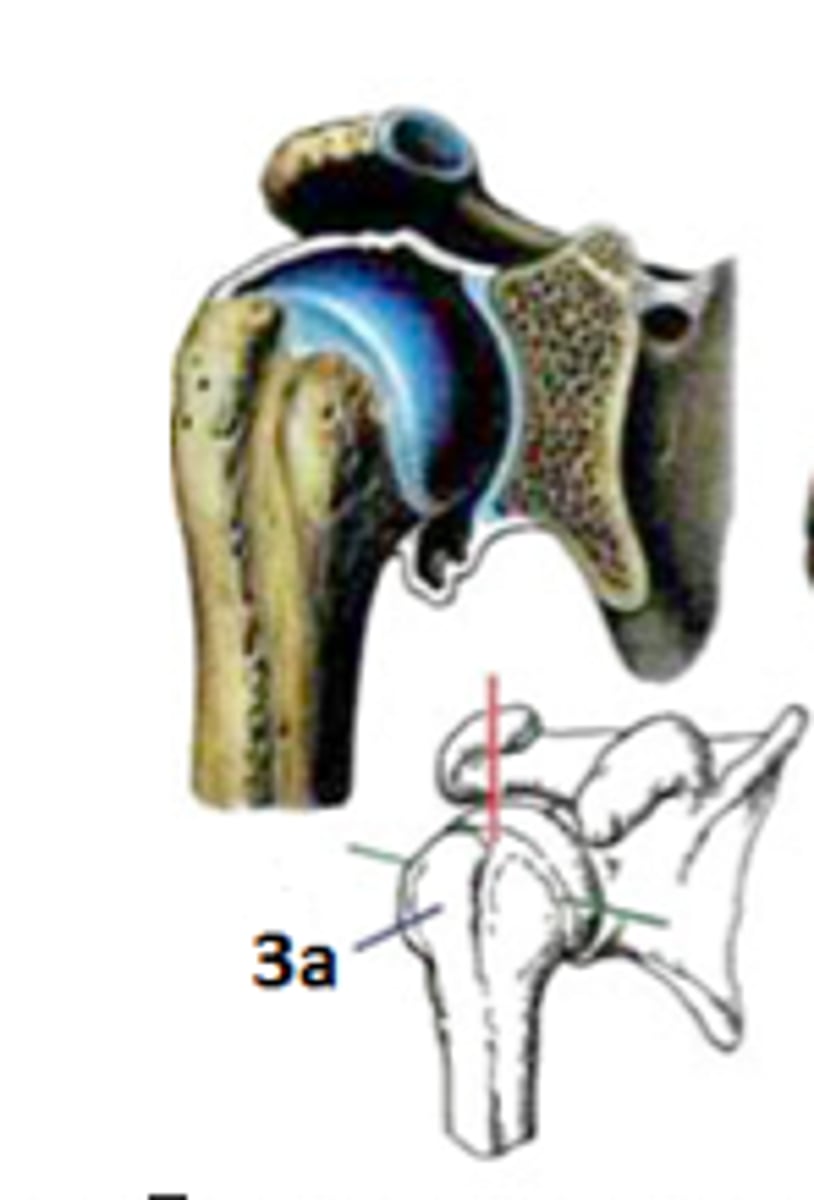

Art. Spheroidea

Art. Cotylica

Art. humeri

Art. coxae